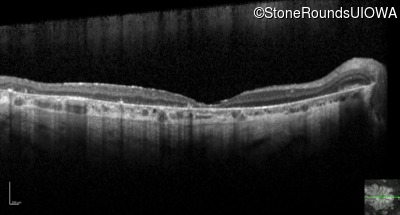

Optical Coherence Tomography - Left - 20/200 +1 sc

Exemplar / OCT Stack

OCT Stack